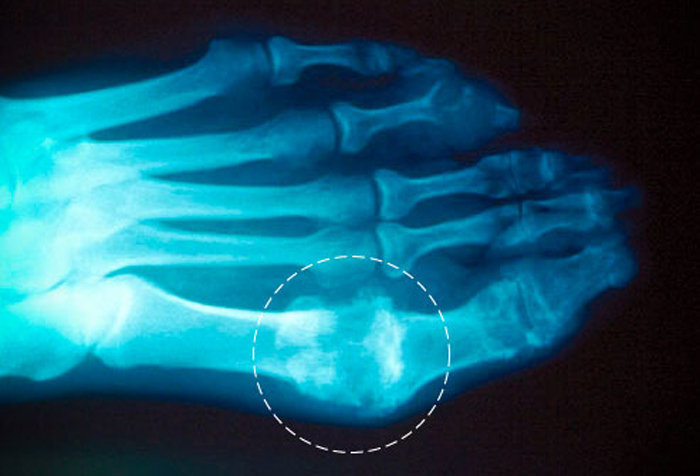

На более поздних стадиях заболевания рекомендуется проводить рентгенографию. Этот метод позволяет выявить тофусы или субкортикальные кисты (образования, возникающие из-за нарушения структуры костной ткани), а также изменения в естественной форме суставов. Рентгенография в данном случае является вспомогательным методом диагностики.